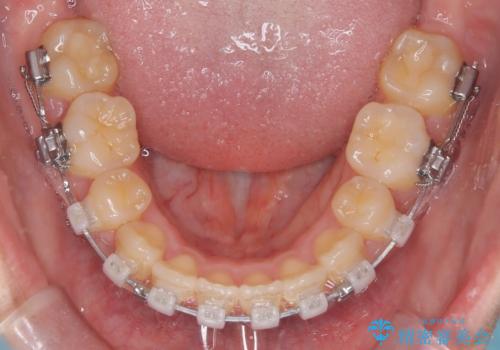

- 矯正装置

- クリア装置

- 治療期間

- 1年6ヶ月

クリア装置とは、当院において最も摩擦を減らした装置のため比較的動きが早く治療がスムーズに進みます。